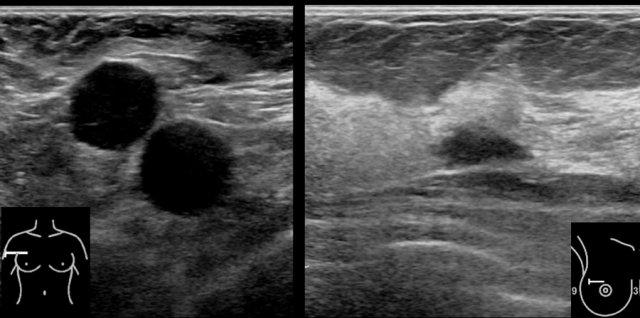

Đây là một ví dụ điển hình về nhiều nang ở một phụ nữ có khối u sờ thấy được ở vú.

Mặc dù có nhiều nang, nhưng chỉ có nang ở trung tâm mới sờ thấy được, vì nang này có hình tròn với dịch chịu áp lực căng bên trong.

Các nang còn lại không sờ thấy được, vì chúng có cảm giác tương tự như mô vú bình thường xung quanh.

Việc phát hiện thêm nhiều nang ở một phụ nữ đến khám vì có nang sờ thấy được là điều rất thường gặp.

Người phụ nữ này có nhiều nang nhỏ ở cả hai vú.

Các nang này không sờ thấy được.